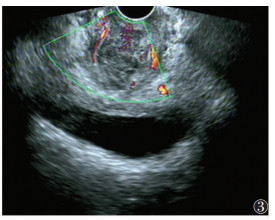

超声共发现病灶区101个(图 1~4),敏感度79.5%,超声诊断与手术结果对照见表 1。经阴道超声诊断的最低敏感度(64.4%)和准确率(79.7%)在阴道,最高敏感度(94.6%)和准确率(97.5%)在直肠子宫陷凹。

| 图 3 39岁,阴道病灶,妇检发现阴道壁紫兰色结节,触痛,超声显示阴道下段混合回声区,边界不清,内见细小液性回声区 |

DIE病灶超声表现:呈结节状、片状或不规则形,边界欠清、不规整。可与周边组织粘连;多为低回声区,偶为等、高回声区,内部回声不均匀,可见细小无回声区,透声欠佳,CDFI可见部分病灶散在短杆或点状的穿枝型血流病灶(17/101,16.8%)。

各部位DIE病灶的诊断要点:①宫骶韧带表现为宫颈下段两侧旁结节样或条索样低不规则回声区;宫旁组织、子宫浆膜面病灶呈不规则片状或斑块状低回声,注意与子宫浆膜下肌瘤鉴别。②超声直接在输尿管周围或内部发现明显病灶较困难,伴输尿管扩张的DIE可增加诊断率,本研究中2例均因输尿管扩张而诊断,但需注意排除,如结石、先天性狭窄等梗阻因素。③膀胱病灶由于尿液透声窗衬托,诊断敏感度较高,病灶常见于后壁,呈低回声结节,可局限于膀胱浆膜面,超声可评估病变的侵犯深度。④本研究中经阴道超声对直肠子宫陷凹病灶诊断敏感度和准确率最高,与文献[8]报道一致,直肠子宫陷凹粘连封闭为DIE显著特征,也可表现为不规则低回声区,与子宫后壁分界不清。⑤阴道、直肠、阴道直肠隔DIE病灶常经妇检首先发现,经阴道超声诊断敏感度偏低,表现为局部不规则低回声区,探头触痛,检查中注意分清三者毗邻结构关系,精确定位病灶侵犯部位。直肠病灶常与宫颈后区病变粘连,造成直肠子宫陷凹闭锁。⑥DIE超声表现虽有一定的特征性,但也需与盆腔脏器恶性肿瘤鉴别。DIE病灶对腹膜脏器浸润是从外(浆膜层)向内(肌层),而肿瘤对肠壁脏器的浸润则是自内(黏膜层)向外(浆膜层)。直肠子宫陷凹病灶需与肿瘤的腹膜转移灶鉴别,两者表现相似,但肿瘤结节的外形较规则,CDFI血流信号丰富,而DIE形态多呈不规则斑片状,CDFI血流信号稀少;且转移瘤常伴腹腔积液,结合其他辅助检查可发现相关原发肿瘤,有助于确诊。

各部位DIE病灶的诊断要点:①宫骶韧带表现为宫颈下段两侧旁结节样或条索样低不规则回声区;宫旁组织、子宫浆膜面病灶呈不规则片状或斑块状低回声,注意与子宫浆膜下肌瘤鉴别。②超声直接在输尿管周围或内部发现明显病灶较困难,伴输尿管扩张的DIE可增加诊断率,本研究中2例均因输尿管扩张而诊断,但需注意排除,如结石、先天性狭窄等梗阻因素。③膀胱病灶由于尿液透声窗衬托,诊断敏感度较高,病灶常见于后壁,呈低回声结节,可局限于膀胱浆膜面,超声可评估病变的侵犯深度。④本研究中经阴道超声对直肠子宫陷凹病灶诊断敏感度和准确率最高,与文献[8]报道一致,直肠子宫陷凹粘连封闭为DIE显著特征,也可表现为不规则低回声区,与子宫后壁分界不清。⑤阴道、直肠、阴道直肠隔DIE病灶常经妇检首先发现,经阴道超声诊断敏感度偏低,表现为局部不规则低回声区,探头触痛,检查中注意分清三者毗邻结构关系,精确定位病灶侵犯部位。直肠病灶常与宫颈后区病变粘连,造成直肠子宫陷凹闭锁。⑥DIE超声表现虽有一定的特征性,但也需与盆腔脏器恶性肿瘤鉴别。DIE病灶对腹膜脏器浸润是从外(浆膜层)向内(肌层),而肿瘤对肠壁脏器的浸润则是自内(黏膜层)向外(浆膜层)。直肠子宫陷凹病灶需与肿瘤的腹膜转移灶鉴别,两者表现相似,但肿瘤结节的外形较规则,CDFI血流信号丰富,而DIE形态多呈不规则斑片状,CDFI血流信号稀少;且转移瘤常伴腹腔积液,结合其他辅助检查可发现相关原发肿瘤,有助于确诊。